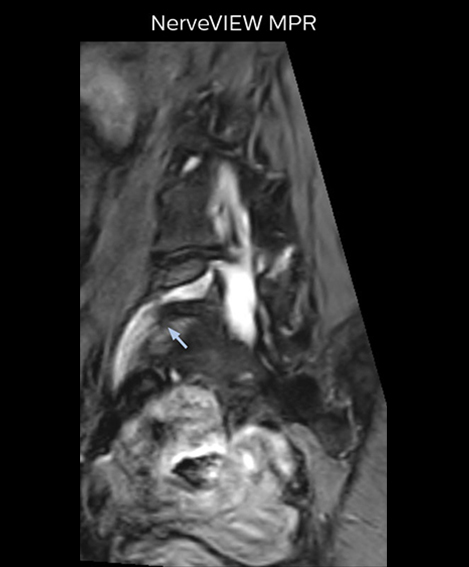

“In such case, we would then browse through axial T2-weighted MR images slice by slice and mentally reconstruct the actual situation based on both radiculography and MRI. Fortunately, NerveVIEW can now very well show nerve courses and presence of nerve compression or edema in one single image series.” “We have often seen NerveVIEW directly depict details of the nerve compression that were not observed by radiculography. Therefore, we think that with NerveVIEW we can reduce the number of invasive examinations, especially for some patients with lumbar plexus symptoms.”

“Before NerveVIEW, diagnosis by MRI alone was sometimes difficult, unless there was a strong suspicion based on clinical symptoms,” says Shoji Yabuki, MD, DMSc, Orthopedic surgeon at Fukushima Medical University School of Medicine. “This is why we routinely perform selective lumbosacral radiculography (nerve root block) and x-ray in such cases. However, radiculography can only depict nerves as far as the contrast agent reaches. When a nerve is distorted by compression, the contrast agent will not pass through this compressed area, preventing us from evaluating the full nerve compression.”

“For example, in sagittal images, when the presence of fat is observed in the intervertebral foramen, it suggests that there is a margin around the nerve. Similarly, the absence of fat indicates that the nerve is being compressed. So, we used to deduce nerve compression indirectly. With NerveVIEW, however, we can observe the condition of the nerves directly, regardless of the presence or absence of fat. We always prefer such direct observation of anatomy over having to make an inference about it.”

“Although symptoms of typical disc herniation and atypical hernia are very similar, the actual site of herniation is different. It is therefore important to characterize the nerve’s condition both inside and outside of the intervertebral foramina. “Conversely, if we see no abnormality in NerveVIEW, we can assume at least that there is no severe condition that requires surgery. Like this, it can help us avoid unnecessary surgery. NerveVIEW can have a tremendous impact in this way.”